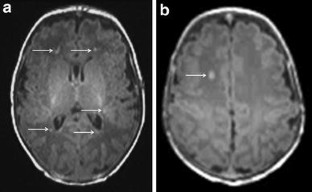

Fig. 1